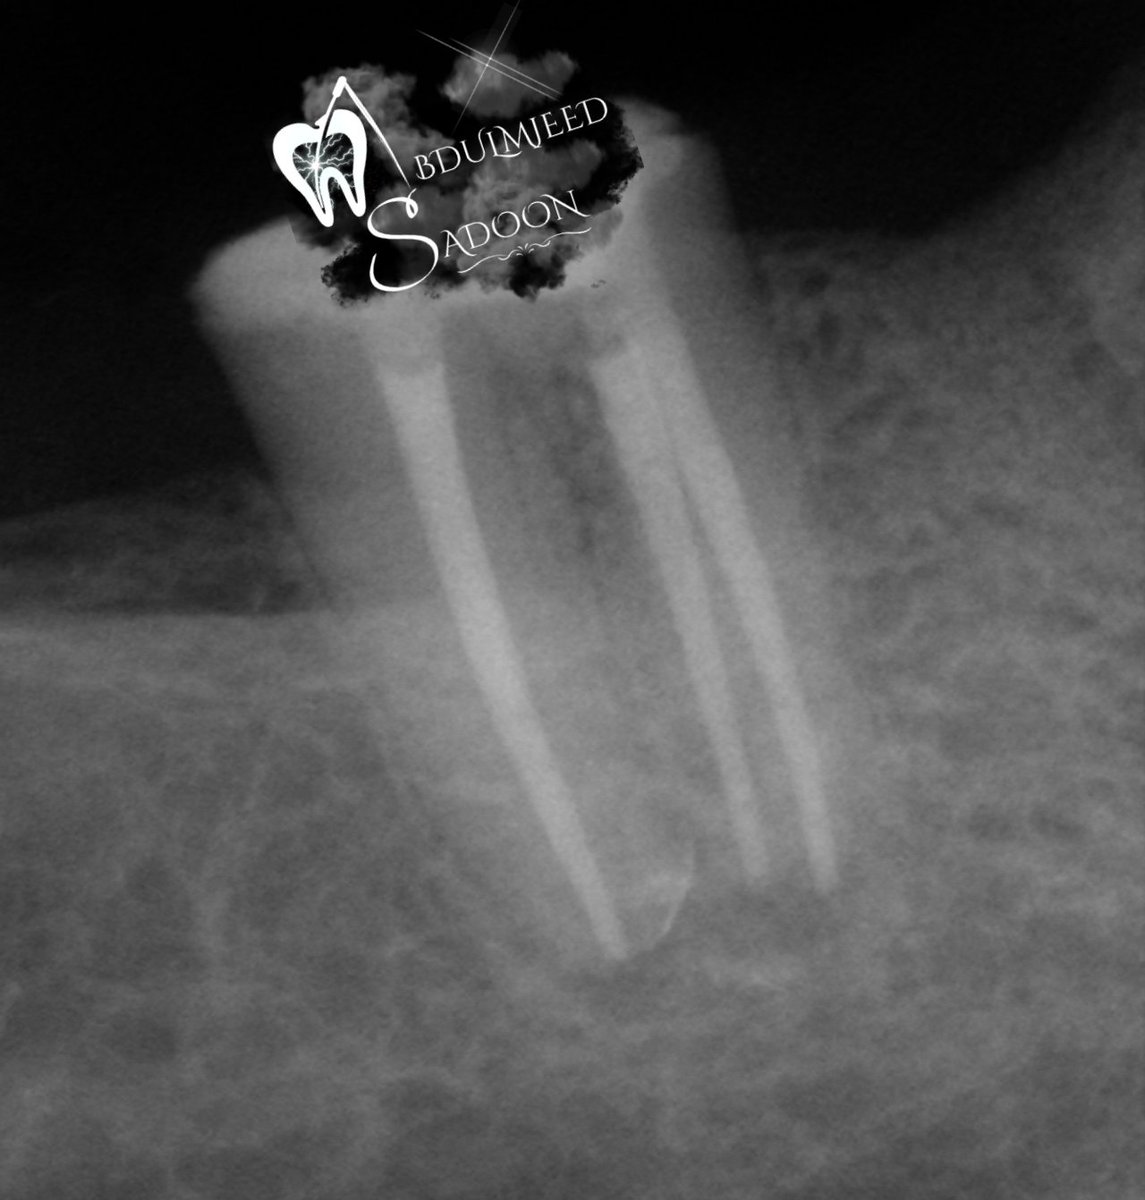

إعادة علاج لحالة ضرس سفلي خلفي Non-surgical Retreatment in mandibular 2nd molar with a C-shaped Root canal system. The difficulty that usually encountered in such cases, is how to disinfect properly without removing too much dentin that could cause strip perforation. Also, how

إعادة علاج لحالة ضرس سفلي خلفي

Non-surgical Retreatment in mandibular 2nd molar with a C-shaped Root canal system.

The difficulty that usually encountered in such cases, is how to disinfect properly without removing too much dentin that could cause strip perforation. Also, how